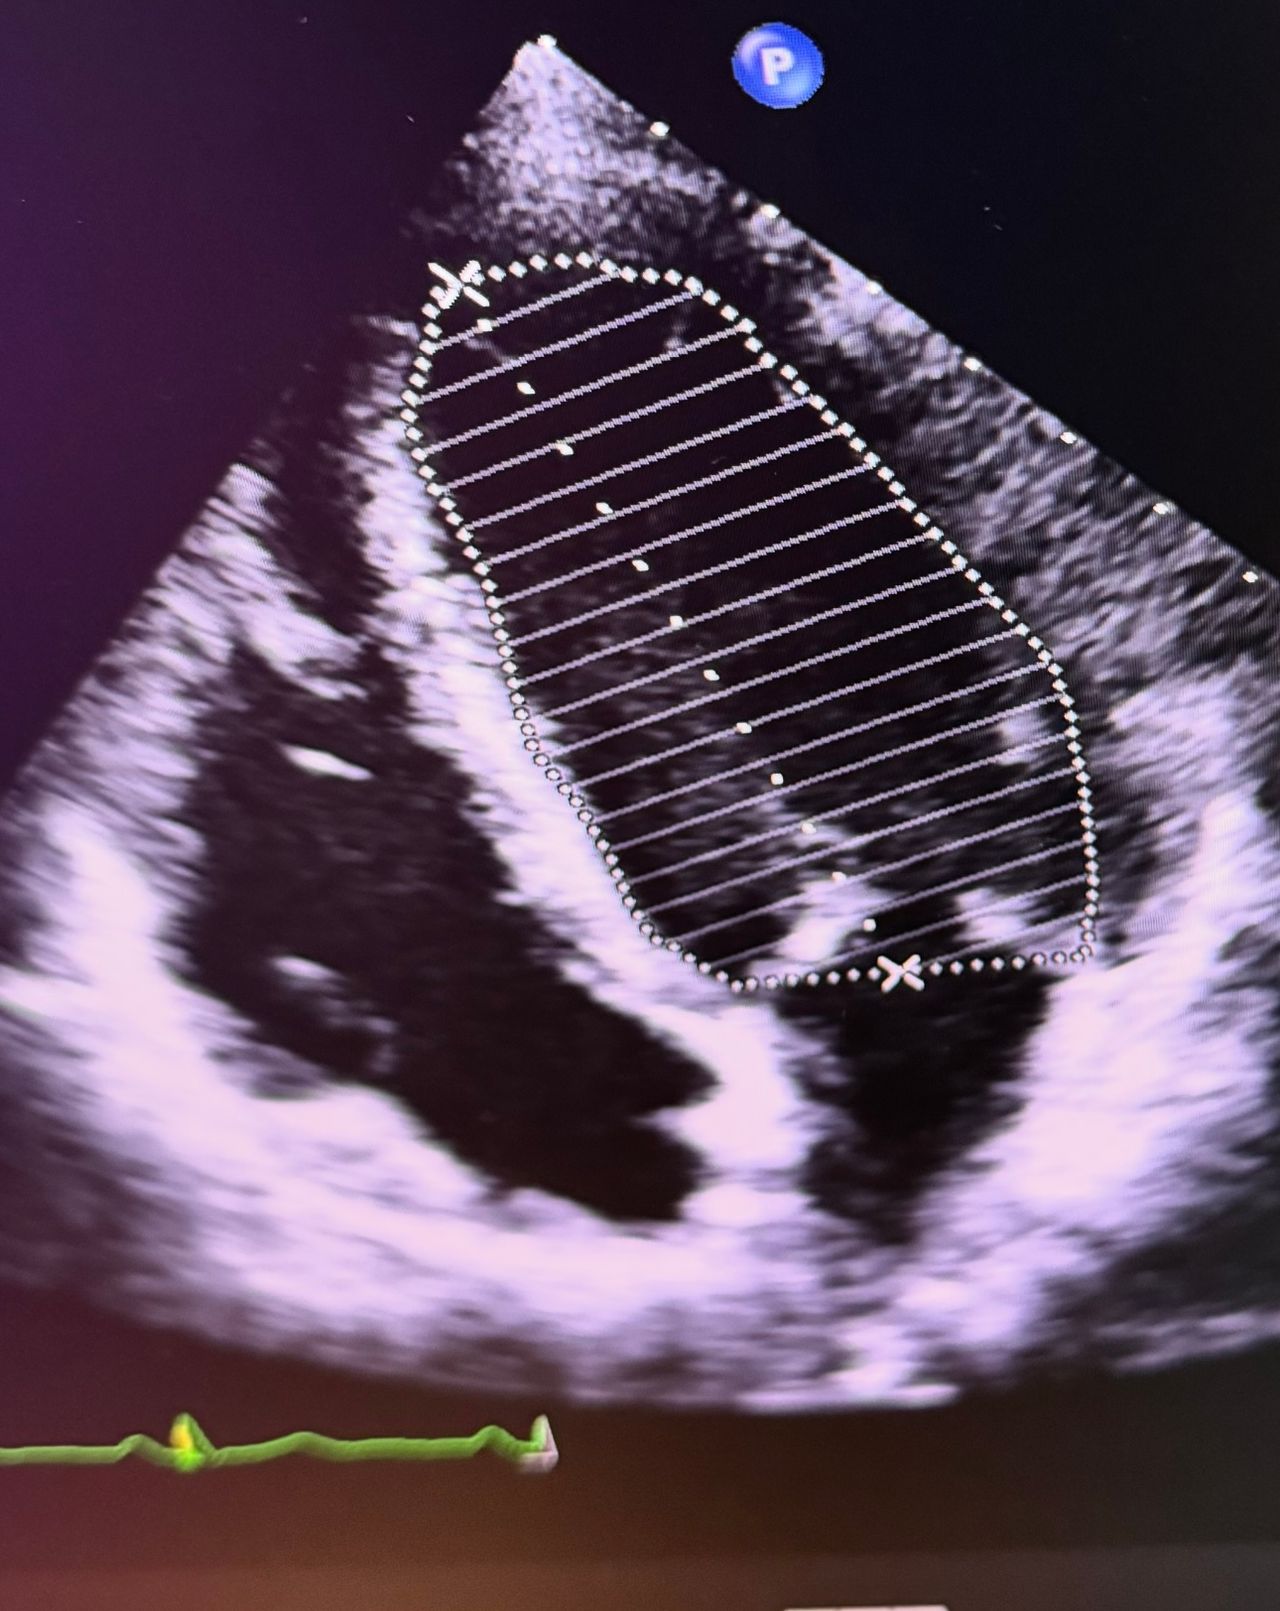

• Ecocardiogramma

130 €

• Visita cardiologica + ECG + ecocardiogramma

180 €